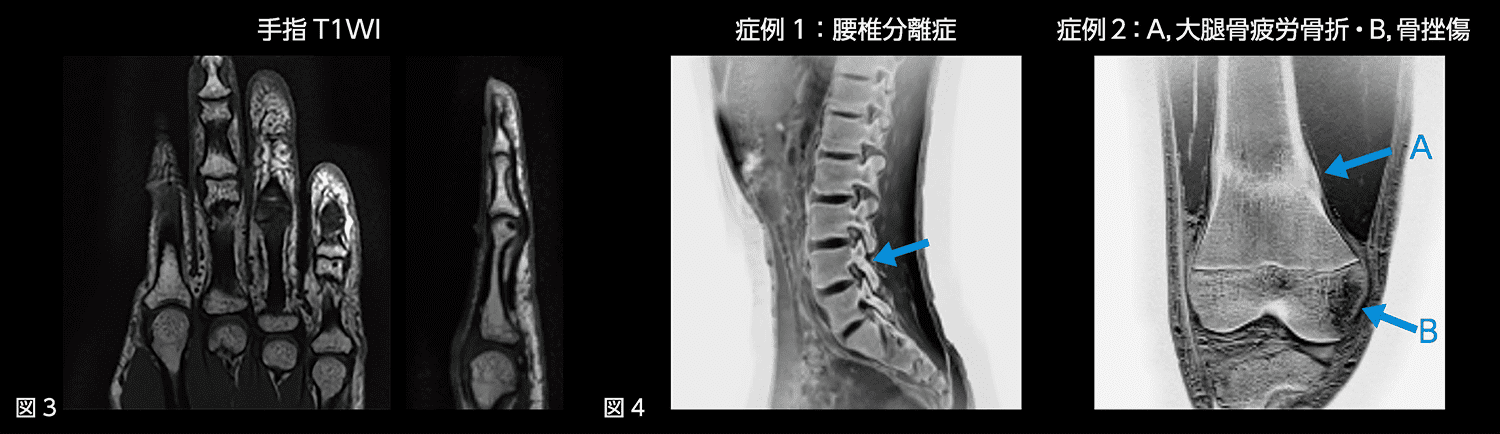

AiCEによる高分解能画像は整形領域でも有用です。AiCEを使用することで2Dでありながら1mmという薄いスライス厚での撮像も可能です(図3)。フレキシブルコイルで撮像可能なので、膝関節や肩関節、手関節など全身のあらゆる部位で高分解能画像を得ることができます。

また、最近の試みとしてT2*WIで複数エコーを収集することにより、骨構造の観察を目的とした画像も提供しています。複数回の撮像が必要となりますが、AiCEを適用することにより、臨床でも使用可能な撮像時間に抑えつつ、高いSNRを実現できています(図4)。画像提供先の医師からも好評で、整形領域において付加価値のある画像ではないかと考えています。